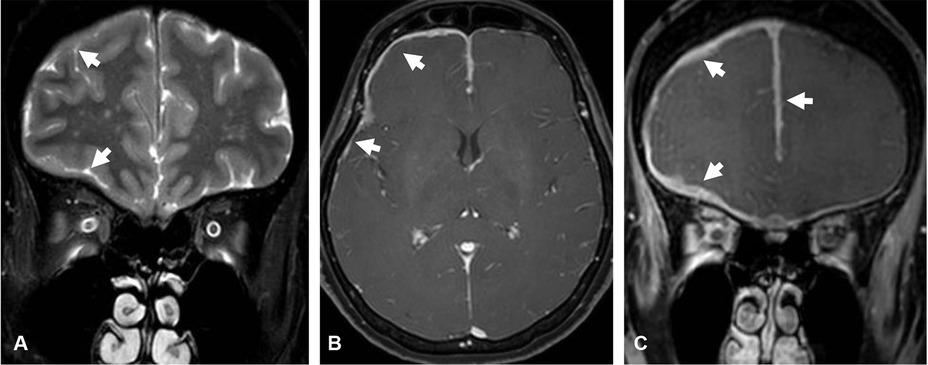

Figure 2

Primary dural lymphoma. Coronal T2-weighted image (A) shows hyperintense undulated thickened dura along the right cerebral convexity, anterior cranial fossa, and anterior falx cerebri (arrow). Axial (B) and coronal (C) gadolinium-enhanced T1-weighted images show homogeneously enhanced dural thickening.

Most of dural thickening involved supratentorium in both groups (96% in idiopathic HP group, and all patients in secondary HP group). Secondary HP group significantly had dural thickening at anterior and middle cranial fossae (55%) (Figure 3) as compared to idiopathic HP patients (13%), P = 0.033. There was no secondary HP patient having posterior fossa dural thickening (Table 3).

Figure 3

IgG4-related pachymeningitis. Coronal T2-weighted image (A) shows dark intensity dural thickening involving right tentorium cerebelli (arrow). Axial (B) and sagittal (C) gadolinium-enhanced T1-weighted images demonstrate mildly heterogeneous enhancement of the thickened dura involving right medial temporal region, right Meckel’s cave, and along anterior part of right tentorium cerebelli (arrow).